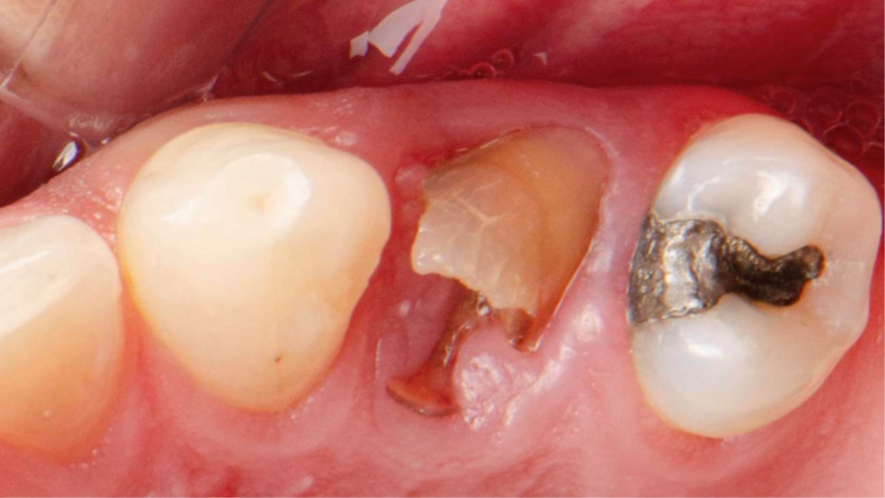

Neste caso relatado a seguir, a fratura do dente 24 levou à indicação de extração atraumática e implante imediato, com uso de biomateriais modernos e fluxo digital completo. O protocolo incluiu implante Due Cone (Implacil Osstem), preenchimento do GAP com Extra Graft, instalação do pilar Ideale definitivo (One Step One Abutment) e posterior coroa em zircônia monolítica.

Após a exodontia do elemento 24 com preservação das paredes ósseas, o preparo foi realizadoseguindo sequência de fresas recomendada para o implante Due Cone, cuja macrogeometriacônica e conexão Morse favorecem alto torque e retenção apical, condições desejáveis para oimplante imediato. A superfície jateada e atacada ao ácido intensifica a adesão celular inicial,contribuindo para osseointegração mais eficiente.